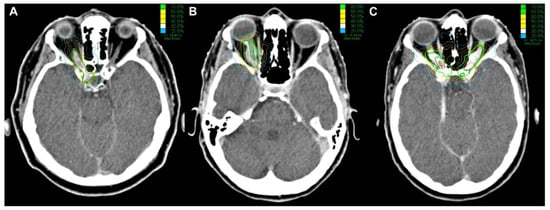

3.5. Optic Nerve Movement and Dose Uncertainties

4.1. Optic Nerve Movement and Dose Uncertainties